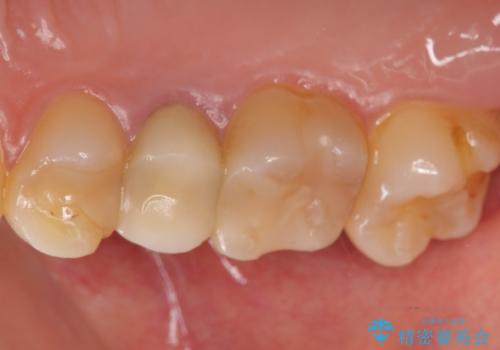

差し歯をもっと自然に 30代女性

- もっと自然にみえるような差し歯にしたいと希望され来院された患者様です。

患者様の天然歯はグラデーションがあり切縁(歯冠の先端)はやや透けていて透明感があるのに対し、前歯(右上1)の差し歯はやや黄色く不透明で単調な色味でした。

患者様のご希望により、右上1はジルコニアクラウン(スペシャル)、右上5はジルコニアクラウン(スタンダード)へやりかえることにしました。

前歯のクラウンは一度修正し、患者様の理想とする色味や形態を追求しました。

天然歯と見紛うほどの自然な仕上がりに喜んで頂けました。

右上1:ジルコニアクラウン スペシャル

右上5:ジルコニアクラウン スタンダード